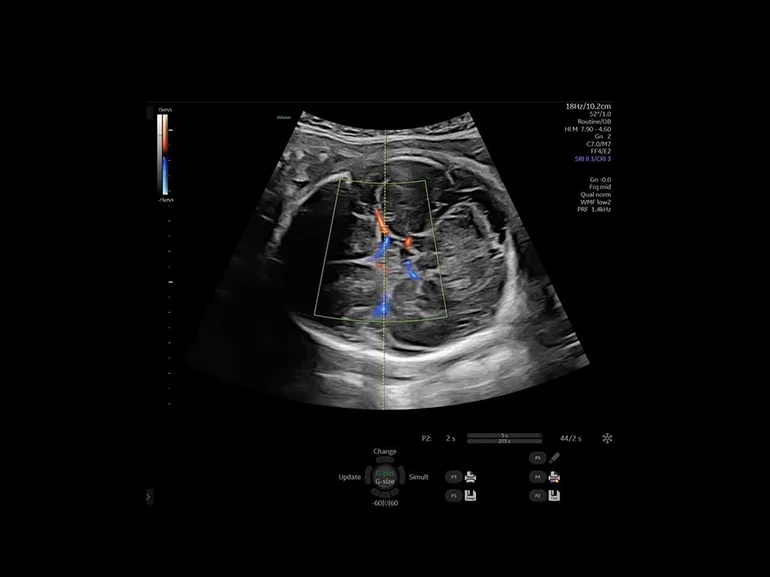

Профили кровотока

Профили кровотока: упростите работу с режимами цветового допплера и импульсно-волнового допплера с помощью настроенного оптимизированного инструмента предустановок.

Импульсно-волновой допплер (PW) используется для исследования отдельных участков сосуда. Визуализирует турбулентный и ламинарный кровотоки. На временной развертке по вертикали отображается скорость потока в исследуемой точке. Потоки, которые двигаются к датчику отображаются выше базовой линии, обратный кровоток (от датчика) – ниже. От режима цветного допплера отличается возможностью более точного выявления направления и скорости кровотока, однако, он малоэффективен при высоких скоростях.